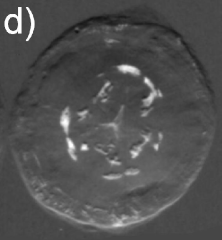

Significant X-ray scattering occurs at the lens surface owing to the air-lens interface. It is responsible for most of the observable features in air exposures, useful to inspect changes in the surface morphology during catarogenesis, as shown in Figs. 1(a) and 1(b) where DEI from healthy and cataractous lenses are compared.

However, to reveal internal density fluctuations the majority of the surface scattering has to be avoided. It is possible by immersing the lens in a medium of nearly the same density of the lens tissue, in this case deionized water. A very clean and uniform image is that obtained in Fig. 1(c) for water exposure of the healthy lens, while large and well defined scattering regions around the nuclei, and also in small amounts at outer regions, are observed in Fig. 1(d) for the cataractous lens.

As summarized in Fig. 2, the image contrast criterions of DEI allows characterization of the scattering properties of the observed internal structures in the lenses. Diffuse-scattering, refraction, and absorption images were collected respectively at the tail (T), shoulder (S), and center (C) of the analyzer window, some good examples are shown in Fig. 3. In the former type of image, the amounts of diffuse-scattering around the internal structures are consistent to the type of scattering expected for an aggregation of tiny precipitates without a well defined boundary, as in Figs. 3(a) and 3(c). On the other hand, refraction images have shown aggregations with dense cores, Fig. 1(d) and 3(d), capable to refract X-rays in an opposite sense of air bubbles, arrow in Fig. 3(f). It indicates that the precipitates are denser than the lens tissue.